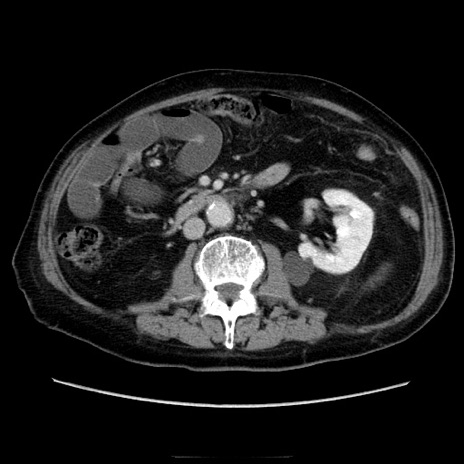

症例21(横断像)

【症例】70歳代男性

【主訴】腹痛

【現病歴】肝硬変・肝細胞癌にてかかりつけの方。約9時間前に食後より腹痛出現。症状が徐々に増悪し、嘔吐出現したため来院。

【既往歴】肝硬変、肝細胞癌(RFA、TACE後)

【身体所見】意識清明、表情苦悶様、BT 36℃、BP 129/78mmHg、P 88bpm、SpO2 97%(RA)、右上腹部から心窩部にかけて圧痛あり、反跳痛なし、筋性防御あり。

【データ】WBC 5800、CRP 0.16